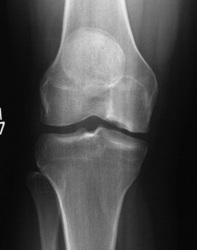

Osteochondral allograft

Principle

Indication

- very large, non contained defects

- previous failed cartilage procedures

Advantage

- restore anatomic contour

- nil donor site morbidity

- viable chondrocytes on fresh allograft < 30 days

Pre and post OCA with HTO